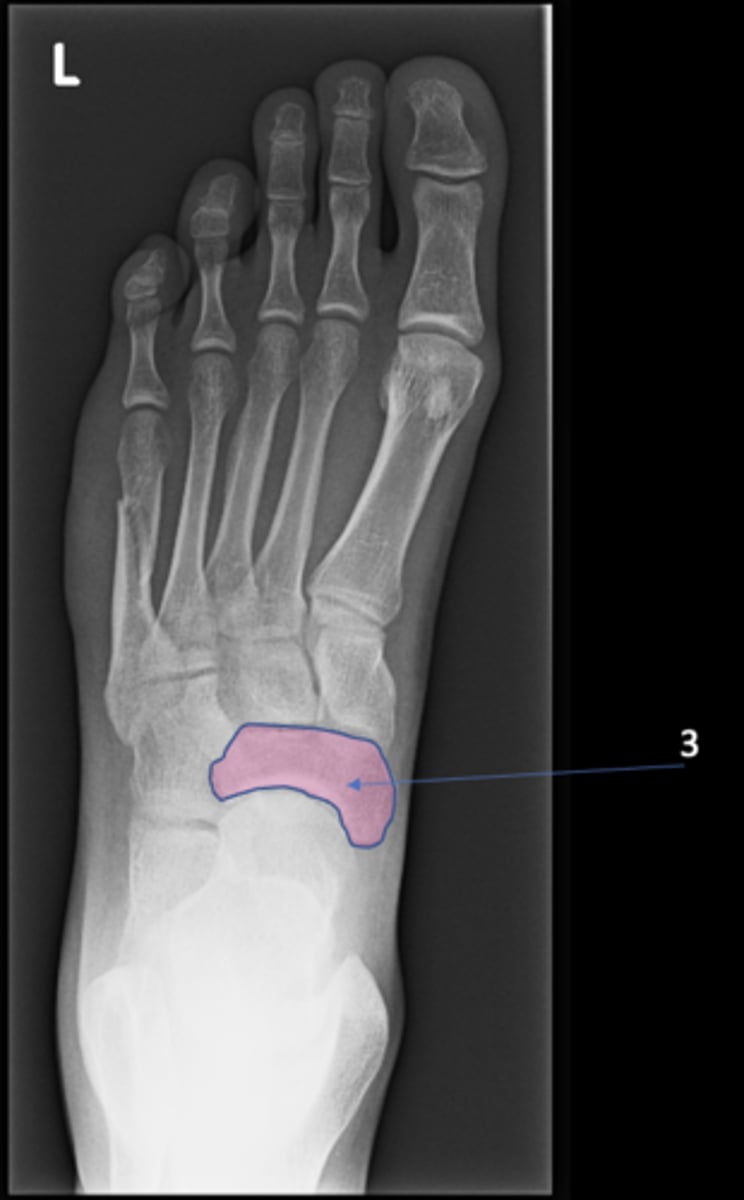

New cards

Left inferior pubic ramus

ID 15

<p>ID 15</p>

15

S1 tubercle

ID 16

<p>ID 16</p>

16